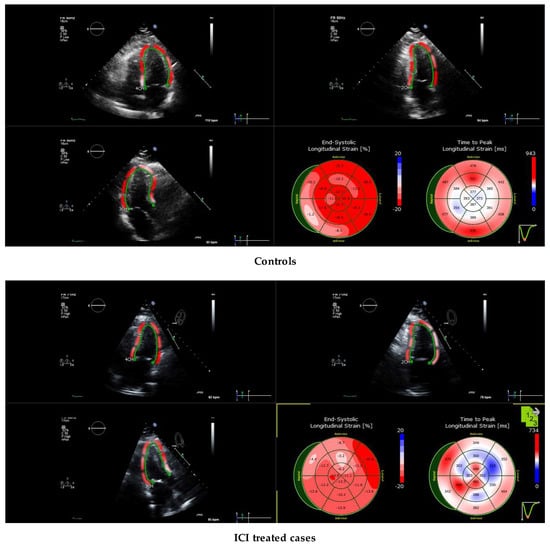

A representative echocardiogram of an ICI-treated patient is shown in Figure 1. Mean longitudinal strain (LS), peak systolic strain rate (SRS) and early diastolic strain rate (SRE) of healthy controls and ICI-treated cases were analyzed. Representative strain curves illustrating changes in strain over time are shown in Figure 2. Strain and strain rate characteristics for regional and global longitudinal contractility are presented in Table 4 and Table 5. As shown in Table 5, LS, SRS and SRE were all significantly lower in the basal and midventricular regions in ICI-treated patients compared to the controls. While the apical region experienced a trend in LS decline (p = 0.054) in ICI-treated patients, there was no statistically significant difference in SRS or SRE in the apical region, which might be suggestive of apical sparing in ICI-treated patients.

Figure 1.

Left ventricular (LV) longitudinal strain imaging of immune checkpoint inhibitor (ICI)-induced cardiomyopathy using speckle tracking echocardiography. The midventricular and apical segments are relatively hypokinetic.

3.7. Cardiac MRI Characteristics

The same cohort of eight ICI-treated patients who underwent echocardiogram analyses were also examined by cardiac MRI and were compared with eight CMR controls. Abnormal LGE patterns were noted on 37.5% (n = 3) of our patients on presentation through CMR. Figure 3 illustrates CMR-based longitudinal strain changes in a single ICI-treated case vs. control. CMR-derived left ventricular (LV) longitudinal strain and strain rate measurements for global and regional myocardial function are presented in Table 6 and Table 7. As seen in Table 7, while there is no statistically significant difference in LV longitudinal strain between ICI-treated patients and controls, the effect size of g = 0.803 suggests the true effect might be large and the lack of significant differences could be due to small sample size and low statistical power. However, ICI-treated patients did experience statistically significant global decreases in LV SRS and SRE compared to the controls. Additionally, cardiac MRI seemed to suggest apical sparing in ICI-treated patients, which was also observed by echocardiography.

Figure 3.

Left ventricular (LV) longitudinal strain imaging of immune checkpoint inhibitor (ICI)-induced cardiomyopathy using cardiac MRI (CMR) under 4 chamber view (4CH). (A) Representative 4CH-CMR image of a control; (B) Representative 4CH-CMR image of an ICI-treated patient. (C) Scatter plots showing the correlation between the mean longitudinal strain and strain rates derived from echocardiography versus CMR. (D) Bland–Altman agreement plots for ICI-induced cardiomyopathy detected on echocardiography compared with CMR for mean longitudinal strain and strain rates. Bland–Altman plots display the difference between values measured by echocardiography and CMR against the mean of these 2 values. The upper and lower dashed lines represent the 95% confidence intervals.